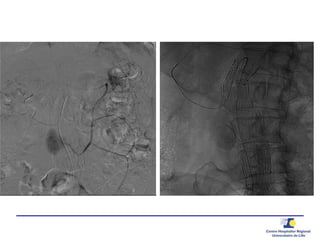

Embolisation par Coil voie

Trans Arterielle

Embolisation transartérielle